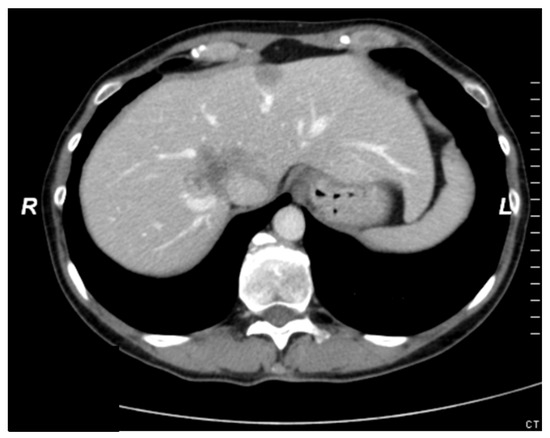

A 58-year-old man was admitted to our hospital in March 2013 with a recurrent single CRLM in segment VIII of the liver involving the VCI (Figure 5). The primary tumor was located in the right colon and has been resected in November 2009 (TNM-classification: pT4, pN2, M0, local R0). The patient received an atypical resection of segment VIII with a segmental resection of the VCI. Reconstruction was performed by interpositioning of a synthetic graft (Gore vascular graft®). The histopathological examination confirmed an infiltration of the vascular wall with tumor negative parenchymal and vascular resection margins (R0 parenchymal and vascular). No postoperative complications occurred and the patient was discharged on day 8 after combined liver and vena cava resection and reconstruction. Tumor recurrence occurred 15 months after liver surgery and involved the liver as well as abdominal lymph nodes. The patient received systemic chemotherapy over 12 months and was re-operated in March 2014 (R0 resection liver, lymph nodes showed complete remission under chemotherapy). Overall survival from the date of liver resection in combination with the VCI resection was 94 months.

Figure 5. Preoperative CT scan (Case report 2); * colorectal liver metastases; ↓ vena cava inferior.